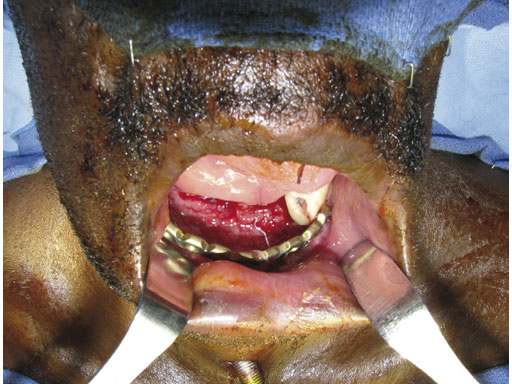

Case 1: A 47-year-old man transferred to the authors hospital approximately 10 days following the resection of a large, benign, locally aggressive odontogenic tumor of the mandible. He was primarily reconstructed with a locking reconstruction plate. The plate dehisced and the patient was unable to eat or swallow leading to his emergent admission to the authors hospital for reconstruction of his mandible with a composite vascularized flap (fibula). The initial internal hardware was removed and a 2.5 mm matrix mandible locking reconstruction plate contoured and applied to the remaining mandibular rami to aid in the reconstruction of the subtotal mandibular defect.

Fig 1 Intraoral situation showing exposed reconstruction plate and exposed edge of native mandible.

Fig 2 Preoperative situation.